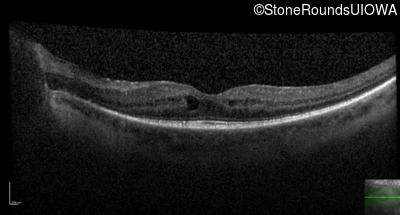

20/30

OCT Stack

20/30 -2